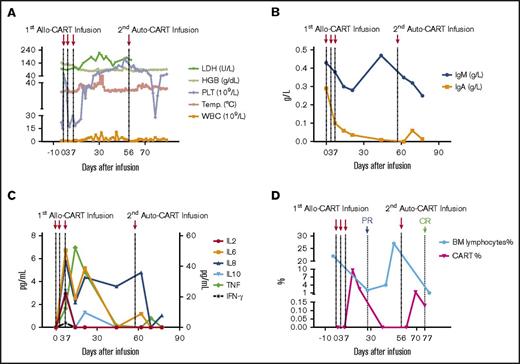

The patient received cyclophosphamide 400 mg/m2 and fludarabine 30 mg/m2 conditioning regimen on day −5 to −3 prior to CAR-T infusion. Allogeneic CAR-T cells from her mother were infused at 0.54 × 106, 0.5 × 106, and 0.9 × 106 per kg of patient’s body weight on days 0, 3, and 7, respectively. The patient developed fever at 38.5°C with scattered maculopapular rashes and pruritus on her back and neck on day 1. Based on prior CAR-T experiences,7-9 she was given 12.5 mg etanercept (anti-TNF-α antibody), and the patient defervesced. Her temperature fluctuated over several days with new onset of facial rashes, and repetitive doses of etanercept were given to control fever (Figure 2A).

Biochemical and immunological kinetics after allo–/auto–CAR-T-cell infusions. (A) Kinetics of hematologic correlates and body temperature. After allo–CAR-T-cell infusions, the body temperature (Temp.) and white blood cell (WBC) count fluctuated continuously, and the platelet count increased gradually. The hemoglobin (HGB) remained steady, and lactate dehydrogenase (LDH) went up correlated with inflammatory response and tumor reduction. (B) The kinetics of IgA and IgM. (C) The kinetics of inflammatory cytokines. The plasma levels of various cytokines were determined by CBA bead array. (D) The kinetics of BM lymphocytes (BM%) and CAR-T cells (CART%). After allo–CAR-T and auto–CAR-T infusions, BM lymphocytes rapidly dropped as did leukemic cell burden, which elicited PR and CR, respectively. The reduction of leukemic cells correlated with CAR-T–cell expansion.

Biochemical and immunological kinetics after allo–/auto–CAR-T-cell infusions. (A) Kinetics of hematologic correlates and body temperature. After allo–CAR-T-cell infusions, the body temperature (Temp.) and white blood cell (WBC) count fluctuated continuously, and the platelet count increased gradually. The hemoglobin (HGB) remained steady, and lactate dehydrogenase (LDH) went up correlated with inflammatory response and tumor reduction. (B) The kinetics of IgA and IgM. (C) The kinetics of inflammatory cytokines. The plasma levels of various cytokines were determined by CBA bead array. (D) The kinetics of BM lymphocytes (BM%) and CAR-T cells (CART%). After allo–CAR-T and auto–CAR-T infusions, BM lymphocytes rapidly dropped as did leukemic cell burden, which elicited PR and CR, respectively. The reduction of leukemic cells correlated with CAR-T–cell expansion.

Because of the patient’s prolonged fevers, broad-spectrum antibiotics and antifungal therapy were initiated. The decrease in immunoglobulin A (IgA) and IgM correlated with B cell aplasia suggestive of CAR-T functionality (Figure 2B). CRS was mild, and no serious biochemical abnormalities were observed (Figure 2A,C). She achieved PR on day 27 with BM hypercellularity of <2% leukemic blasts and MRD of 0.42% by flow cytometry (Figure 2D). On day 50, complete blood count (CBC) returned to normal, and BM evaluation indicated immature lymphocytes at 27% and MRD of 6.71% blasts.

The CBC recovery was accompanied by disappearance of allo–CAR-T cells and increased MRD. Therefore, a second CAR-T course from her own source was initiated. At time of apheresis, the collected cells were 100% of her own based on genotyping, with an absolute lymphocyte count of 0.97 × 109/L and 45% CD3 T cells. Cyclophosphamide 400 mg/m2 and fludarabine 30 mg/m2 conditioning regimen was given on day 51, and autologous CAR-T cells (0.16 x 106/kg) were infused on day 56, which was well tolerated. CAR-T–cell expansion was detected on day 64, and the patient received etanercept for an associated fever. Her temperature returned to normal by day 66. On day 78, 23 days after the auto–CAR-T infusion, BM examination indicated CR by histology and flow cytometry (Figure 2D). Chromosomal analysis showed complete normal phenotype (46, XX) without abnormal clones. Computed tomography (CT) scans of lungs revealed complete resolution from previous infections by day 83 (Figure 3). Because of the lack of matched unrelated donor, and a negative test result for donor specific antibody, the patient subsequently underwent haploidentical hematopoietic stem cell transplantation from the same donor 2 months after the auto–CAR-T infusion.